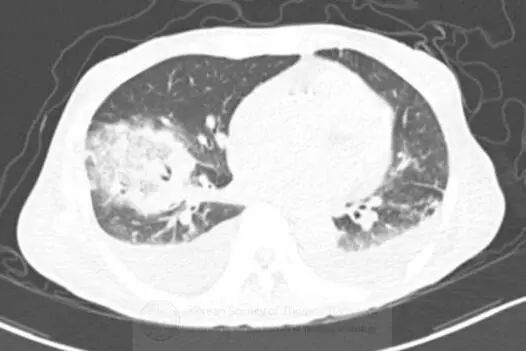

图1胸片示右肺下叶空洞性实变和左肺下叶实变。CT示右肺下叶类圆形实变伴中央磨玻璃影(反晕征),和空洞性病变。可见双侧胸腔积液。

支气管镜活检,真菌菌丝提示毛霉病。

诊断:毛霉病